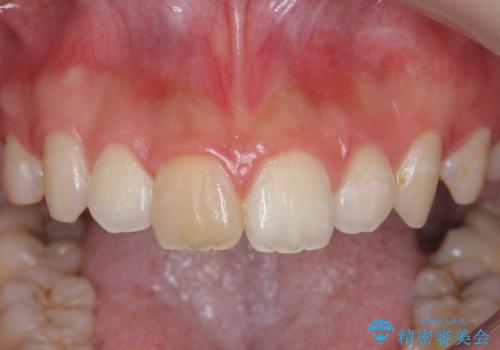

前歯の変色をキレイに セラミッククラウン審美治療

- 前歯の変色が気になる、見た目を改善したい!と審美性の回復を希望され来院されました。

ホワイトニングでは、周囲の歯との色調になじむほどには白くできないため、ジルコニアセラミッククラウンを用いて審美性を回復します。

周囲の歯の色調に調和した審美性の高いセラミッククラウンを製作することができました。